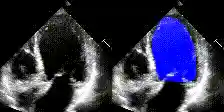

Examples

We show examples of our semantic segmentation for nine distinct patients below. Three patients have normal cardiac function, three have low ejection fractions, and three have arrhythmia. No human tracings for these patients were used by EchoNet-Dynamic.

| Normal | Low Ejection Fraction | Arrhythmia |